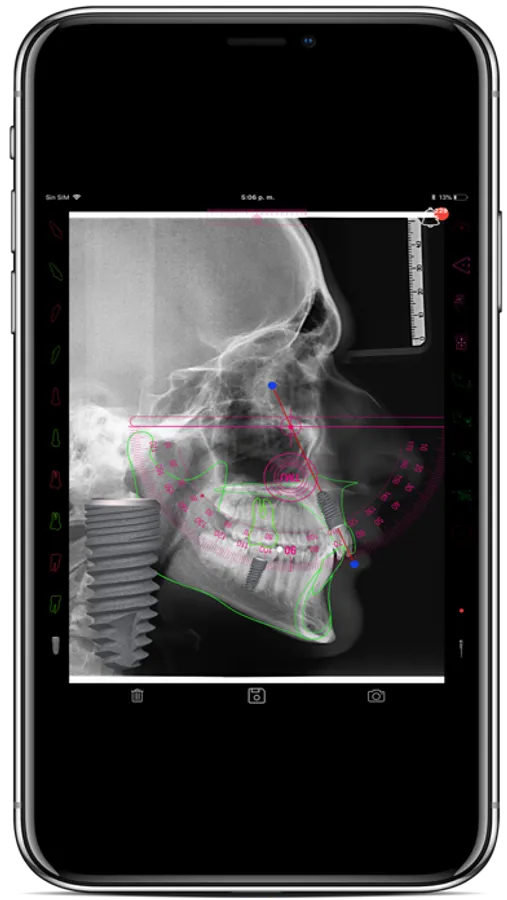

Diseñada para realizar el trazados, lectura diagnóstica y planificación terapéutica de la radiografía lateral de cráneo de manera sencilla y amigable, por medio trazados automáticos con el Touch Control System. Por medio de la digitalización directa y ejecución de los trazados sobre la pantalla del smart phone o en tabletas digitales con pantalla táctil se agiliza y optimiza el proceso.

Con innovadoras ideas en el diagnostico creadas por el Dr. Tatis como los los Equilateros Funcionales de Tatis, la Esfera Cráneo-cervical, el auto-trazado dental y esquelético entre otras funciones más, la exactitud y precisión en el diagnóstico estarán garantizadas.

Funciones adicionales le permitirán realizar planeación de la biomecánica ortodóntica convencional y con mini-implantes, planeación de la restauración en implantología, lectura de la anatomía articular de la A.T.M y su relación con el plano oclusal, captura, almacenamiento y socialización de imágenes en redes entre otras.

h- Calibración y medición de la radiografía lateral de cráneo

i- Digitalización y auto-trazado directo de la cefalometría